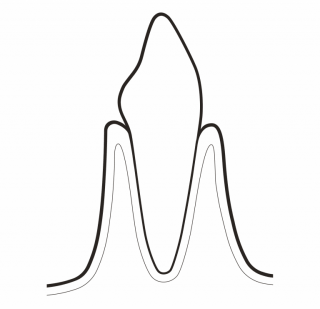

PRESERVE HEALTHY TEETH

GBT minimizes the use of power and hand instrumentation. AIRFLOW® is minimally invasive on all types of dental tissues: dentine, cementum, enamel and gums. Minimal abrasion for maximum comfort: GBT enables the patient to enjoy natural teeth and implants for much longer.